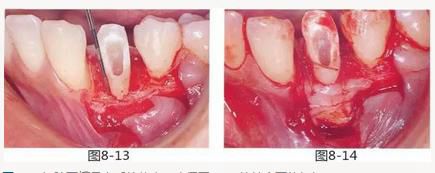

圖8-13 切除牙槽骨之后的狀態(tài)。確保了3mm的健全牙體組織。

圖8-14 為了增加附著齦,進行了結(jié)締組織移植術(shù)。